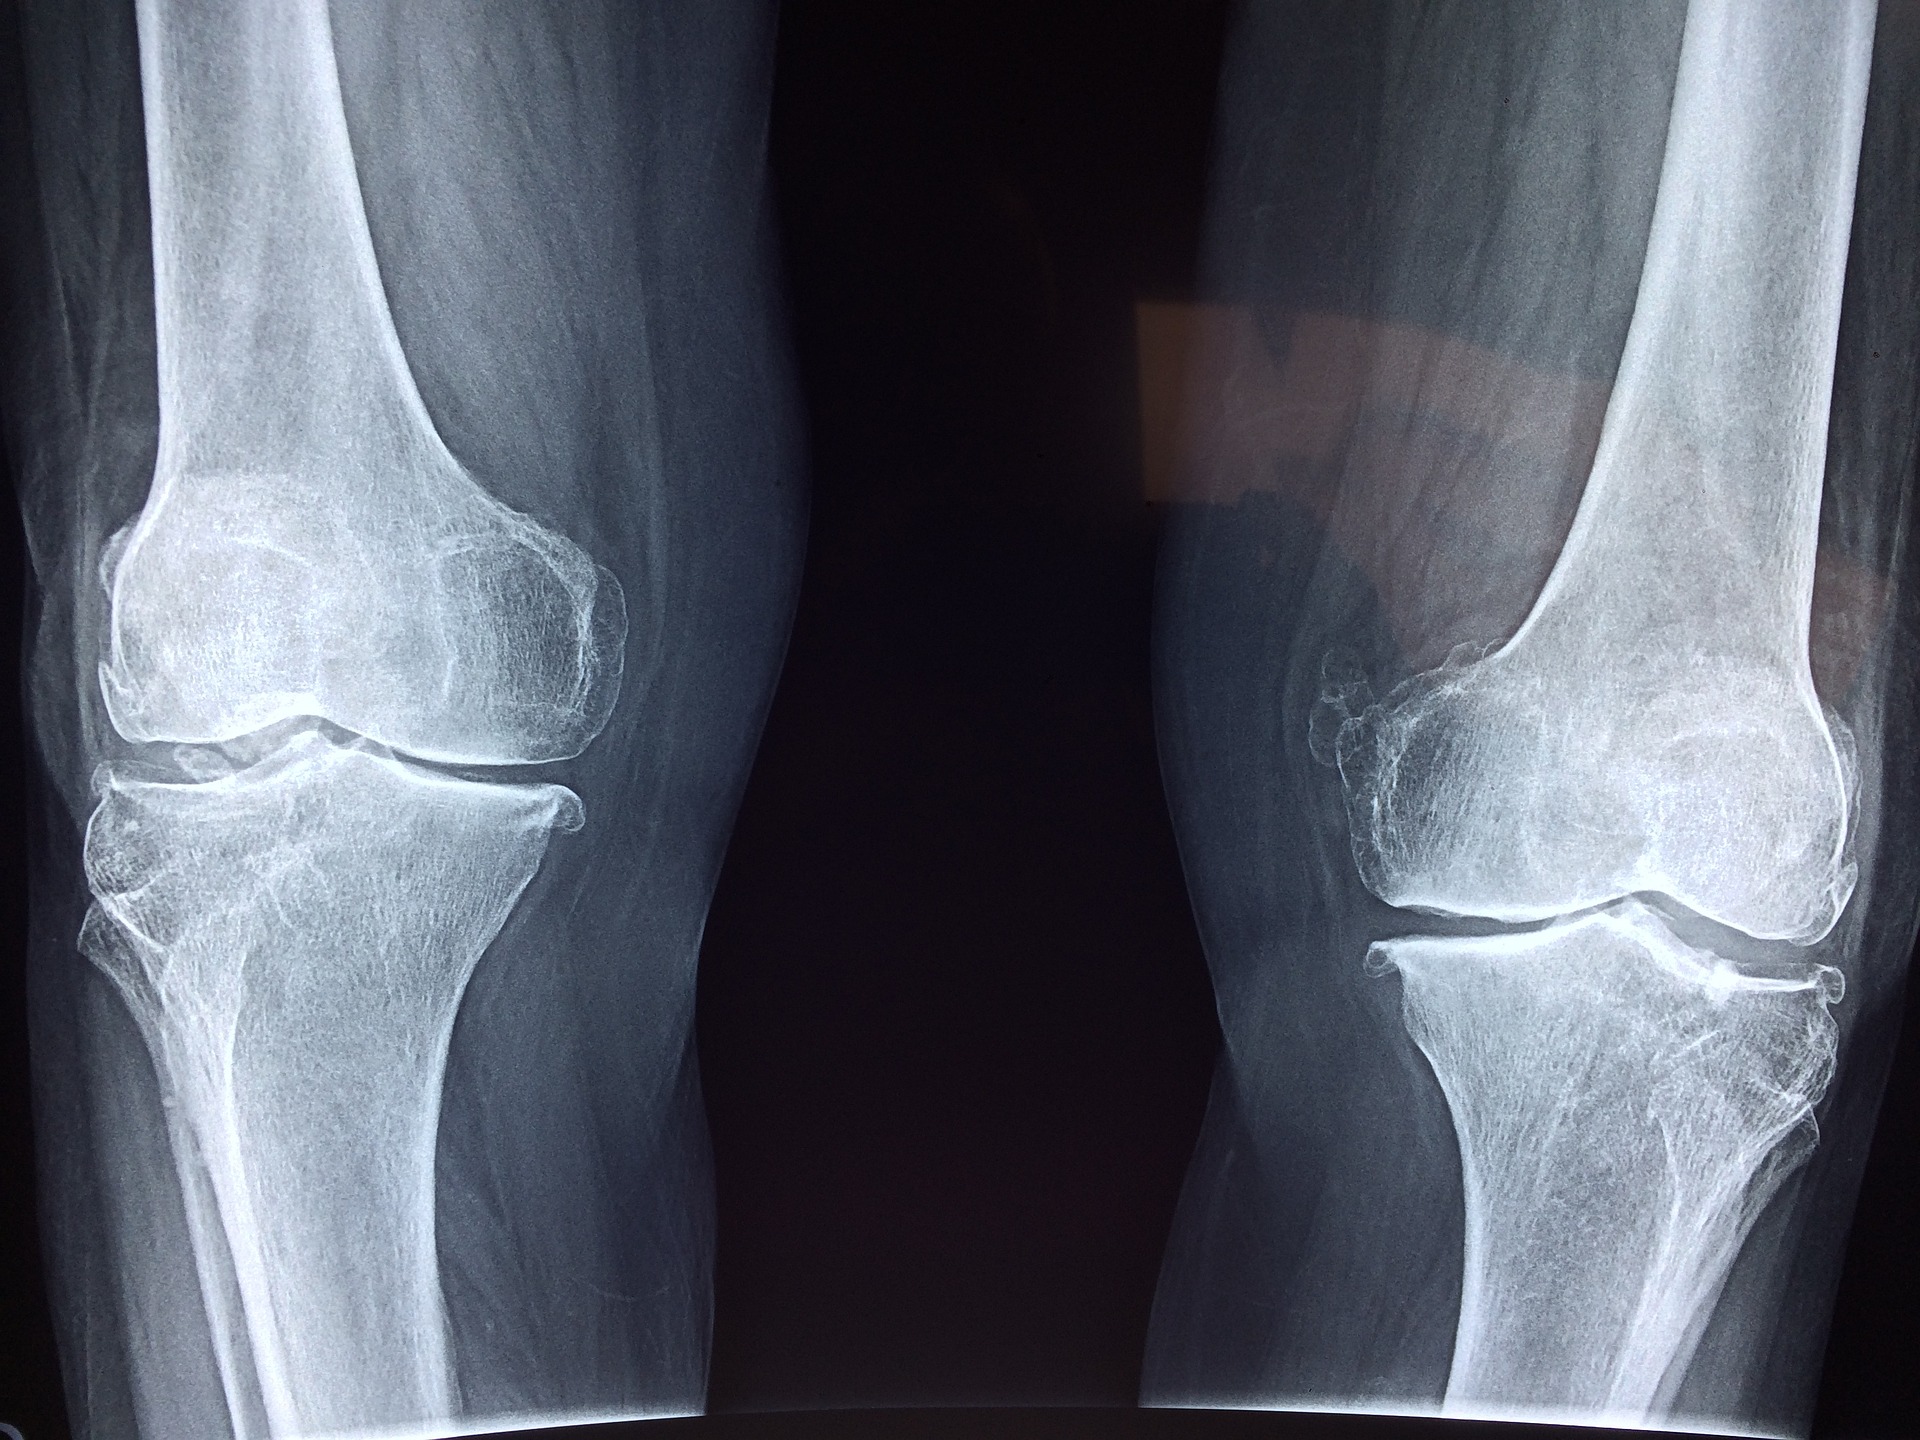

연골 손상과 퇴행성 관절염은 우리 몸의 건강한 기능을 방해하는 질환입니다. 연골은 신체적인 부담 및 나이로 인해 손상이 발생할 수 있는데, 이러한 손상은 상대적으로 긴 시간 동안 진행되며, 적극적으로 예방 조치를 취하지 않는다면 연골의 손상이 계속 진행되어 퇴행성 관절염으로 진행되게 됩니다.

영국 퀸 메리 런던대학교 연구진들은 실험 참가자 70명을 대상으로 2년 동안 매일 500mg의 콜라겐 펩타이드를 섭취하도록 했습니다. 그 결과 시험군에서 무릎 통증의 개선 효과가 나타났다고 합니다.

또한 미국 피츠버그대학 연구팀에서는 폐경 여성 26명을 대상으로 12주간 매일 5g의 콜라겐 펩타이드를 섭취하도록 하였습니다. 그 결과 실험 참가자 전원에게서 골밀도가 증가했고, 골반 골절률 또한 감소했다고 밝혔습니다. 이렇듯 인체에 있어 매우 중요한 역할을 하는 콜라겐은 20대 중반 이후로 체내에서의 합성 능력이 급격히 저하되기 시작하고, 40대 이후부터는 눈에 띄게 줄어든다고 하니 꾸준한 섭취가 필요합니다.